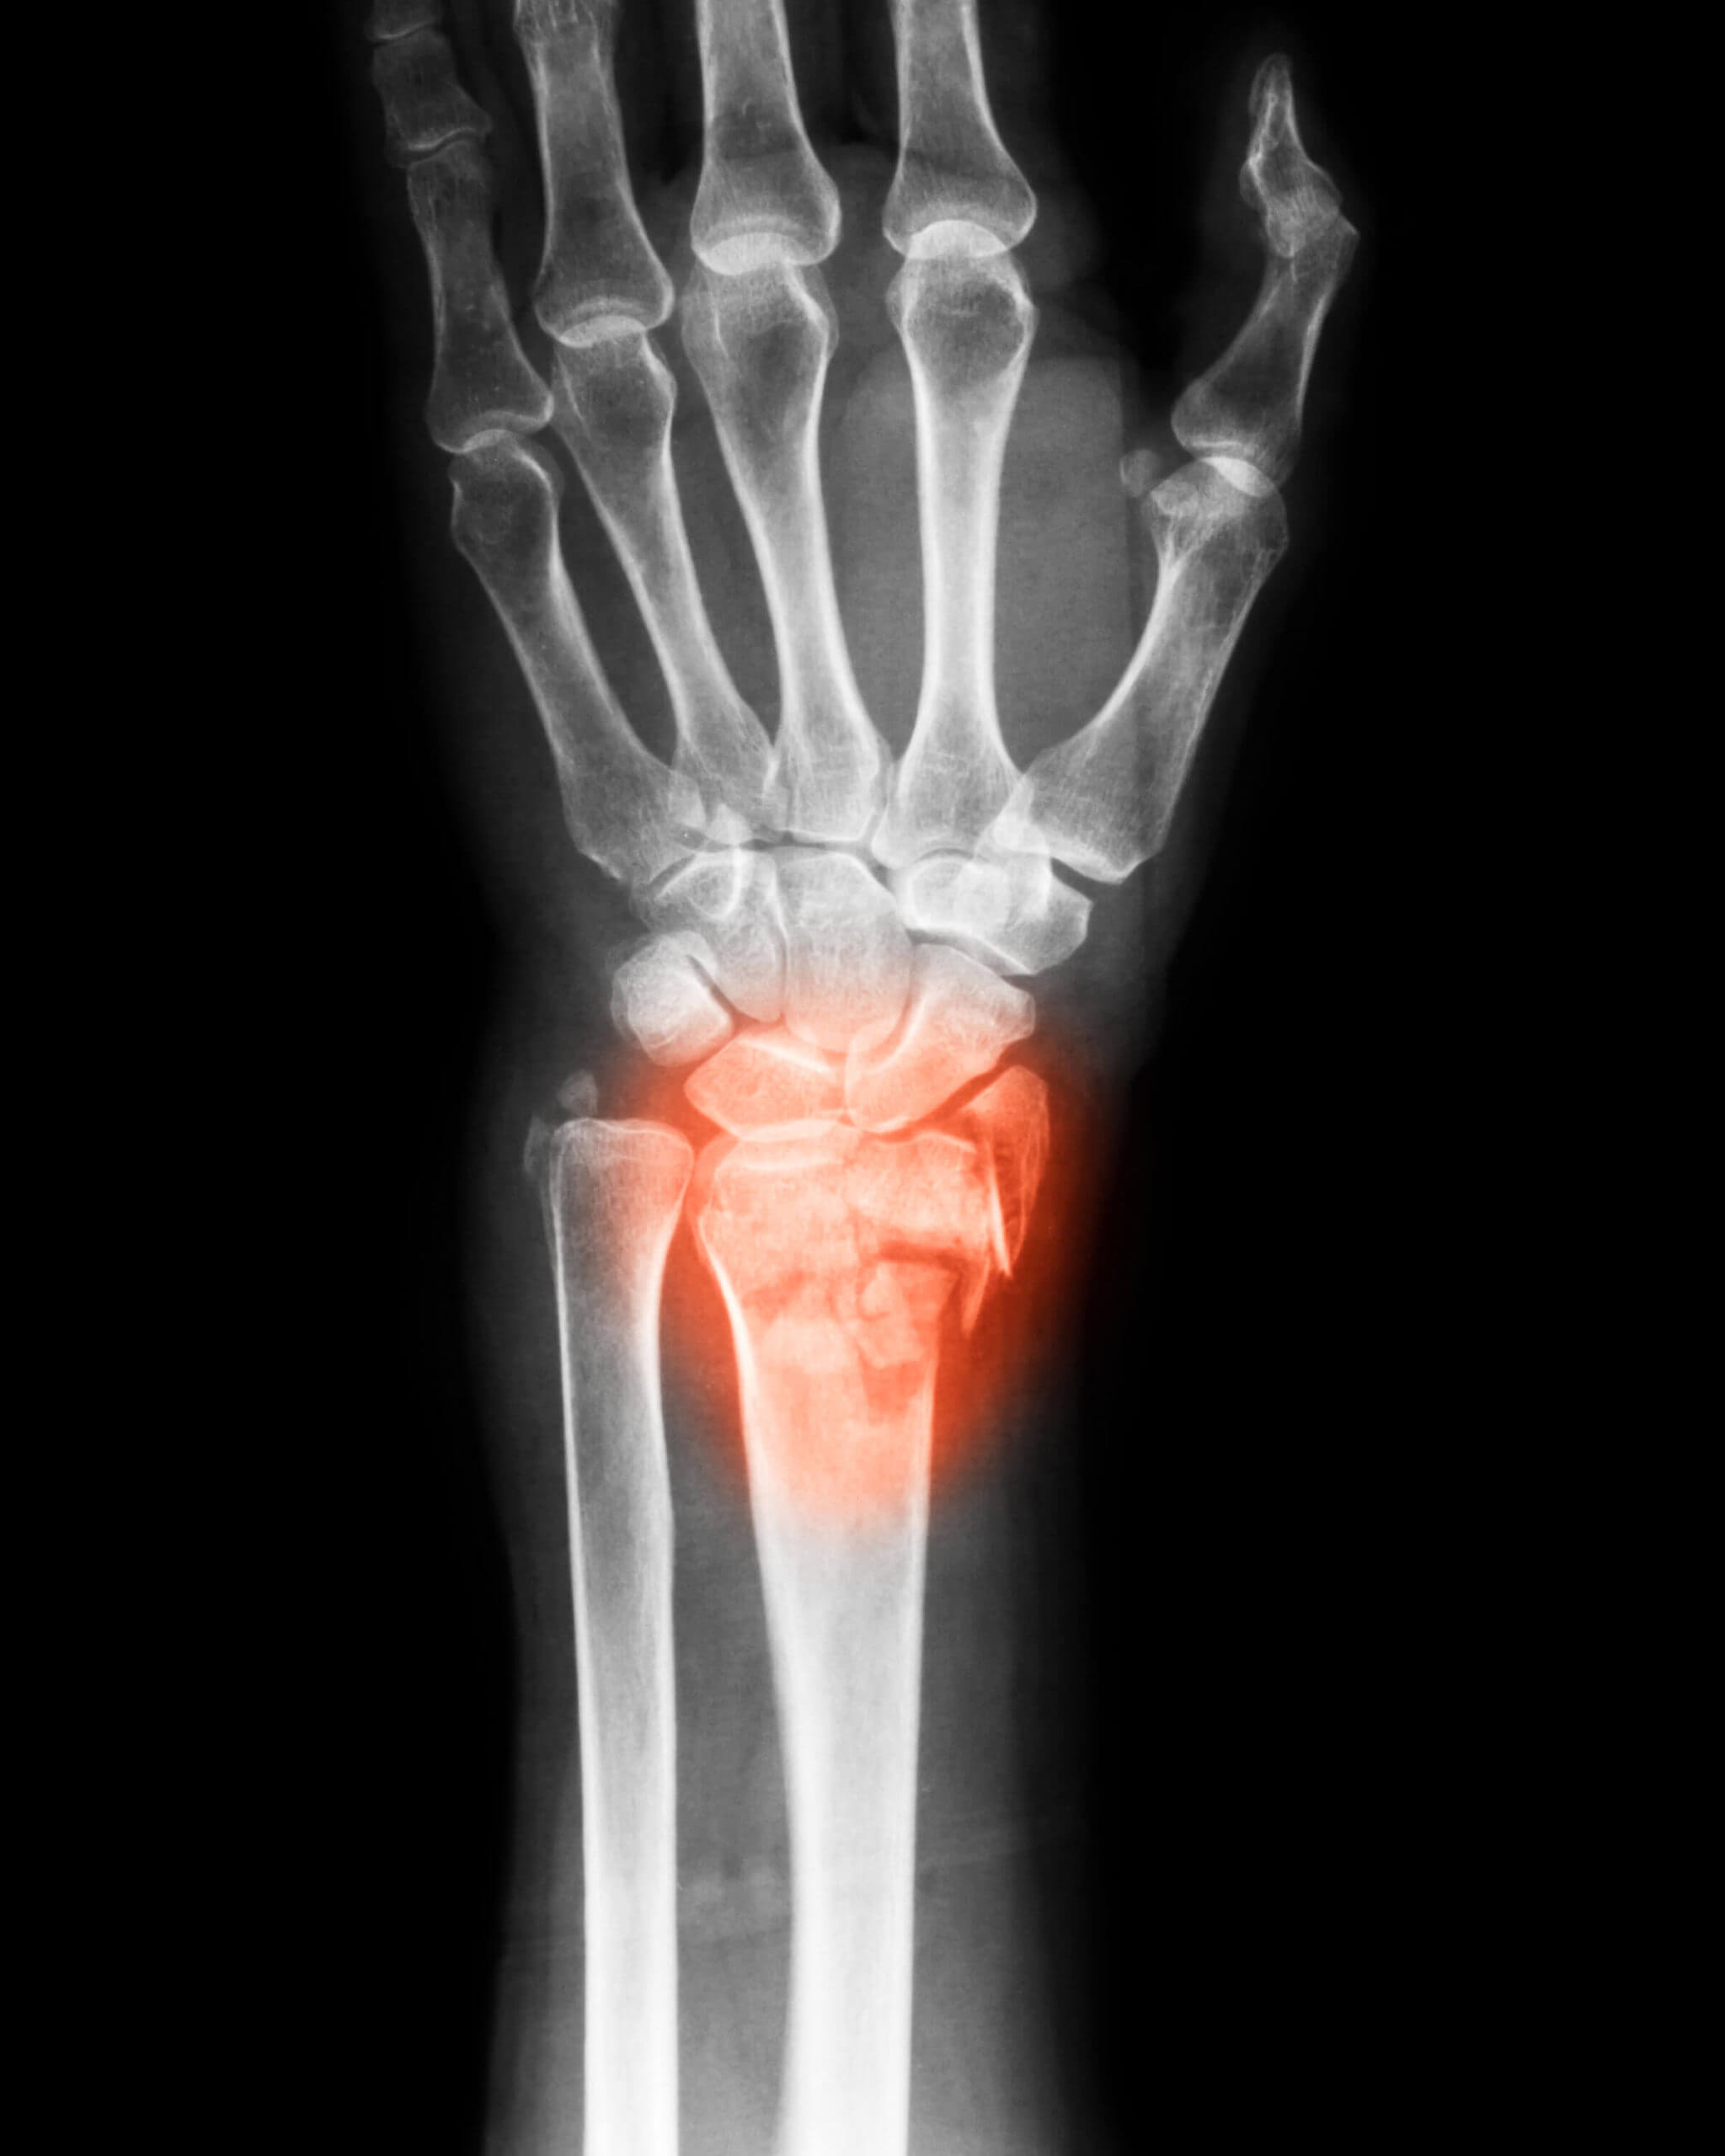

Scaphoid Fracture Symptoms Uk . A scaphoid fracture is a common type of wrist fracture caused by a fall on an outstretched hand. Learn about scaphoid fractures, a type of hand injury caused by falling on an outstretched hand. Symptoms include pain at the base of the thumb, which is worse with use of the hand. Because most scaphoid fractures do not cause the wrist to look broken and many cause only minor symptoms, it can. Following your examination today, your practitioner suspects you have a scaphoid injury or fracture. Swelling and bruising at the injury site is normal and may or. Find out the anatomy, classification, symptoms, investigations, management, and complications of scaphoid fractures. Find out the symptoms, treatment, recovery and contact details from cambridge. Learn how to recognise the. What are the symptoms and how is it diagnosed? It is likely you have had an x. Patients complain of pain in the wrist, there may be slight swelling, pain trying. Learn about scaphoid fractures, the most common carpal bone fracture, caused by a fall on an outstretched hand (foosh).

What are the symptoms and how is it diagnosed? Because most scaphoid fractures do not cause the wrist to look broken and many cause only minor symptoms, it can. Symptoms include pain at the base of the thumb, which is worse with use of the hand. Learn how to recognise the. Following your examination today, your practitioner suspects you have a scaphoid injury or fracture. A scaphoid fracture is a common type of wrist fracture caused by a fall on an outstretched hand. Patients complain of pain in the wrist, there may be slight swelling, pain trying. Learn about scaphoid fractures, the most common carpal bone fracture, caused by a fall on an outstretched hand (foosh). Learn about scaphoid fractures, a type of hand injury caused by falling on an outstretched hand. Swelling and bruising at the injury site is normal and may or.